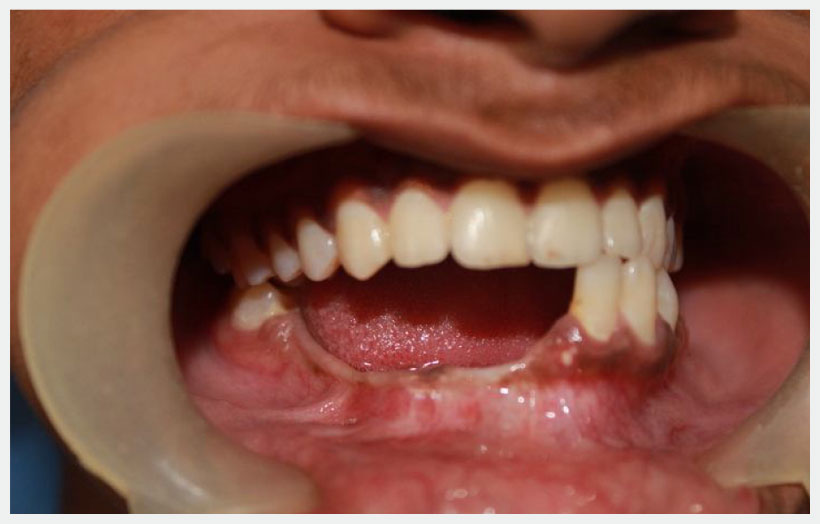

18 year old male patient came with chief complain of Swelling over Rt side of lower jaw. He was diagnosed as Benign Ossifying fibroma. Surgery was made in Feb 2013 for excision of lesion and reconstruction using Iliac crest cortico-cancellous bone graft from right side. Bone graft fixed to the defect using a reconstruction plate. After 1 year we can see adequate bone formation at the defect side. He is planed for replacement of missing teeth using 3 Alpha Dent 5×13 mm classic implants.